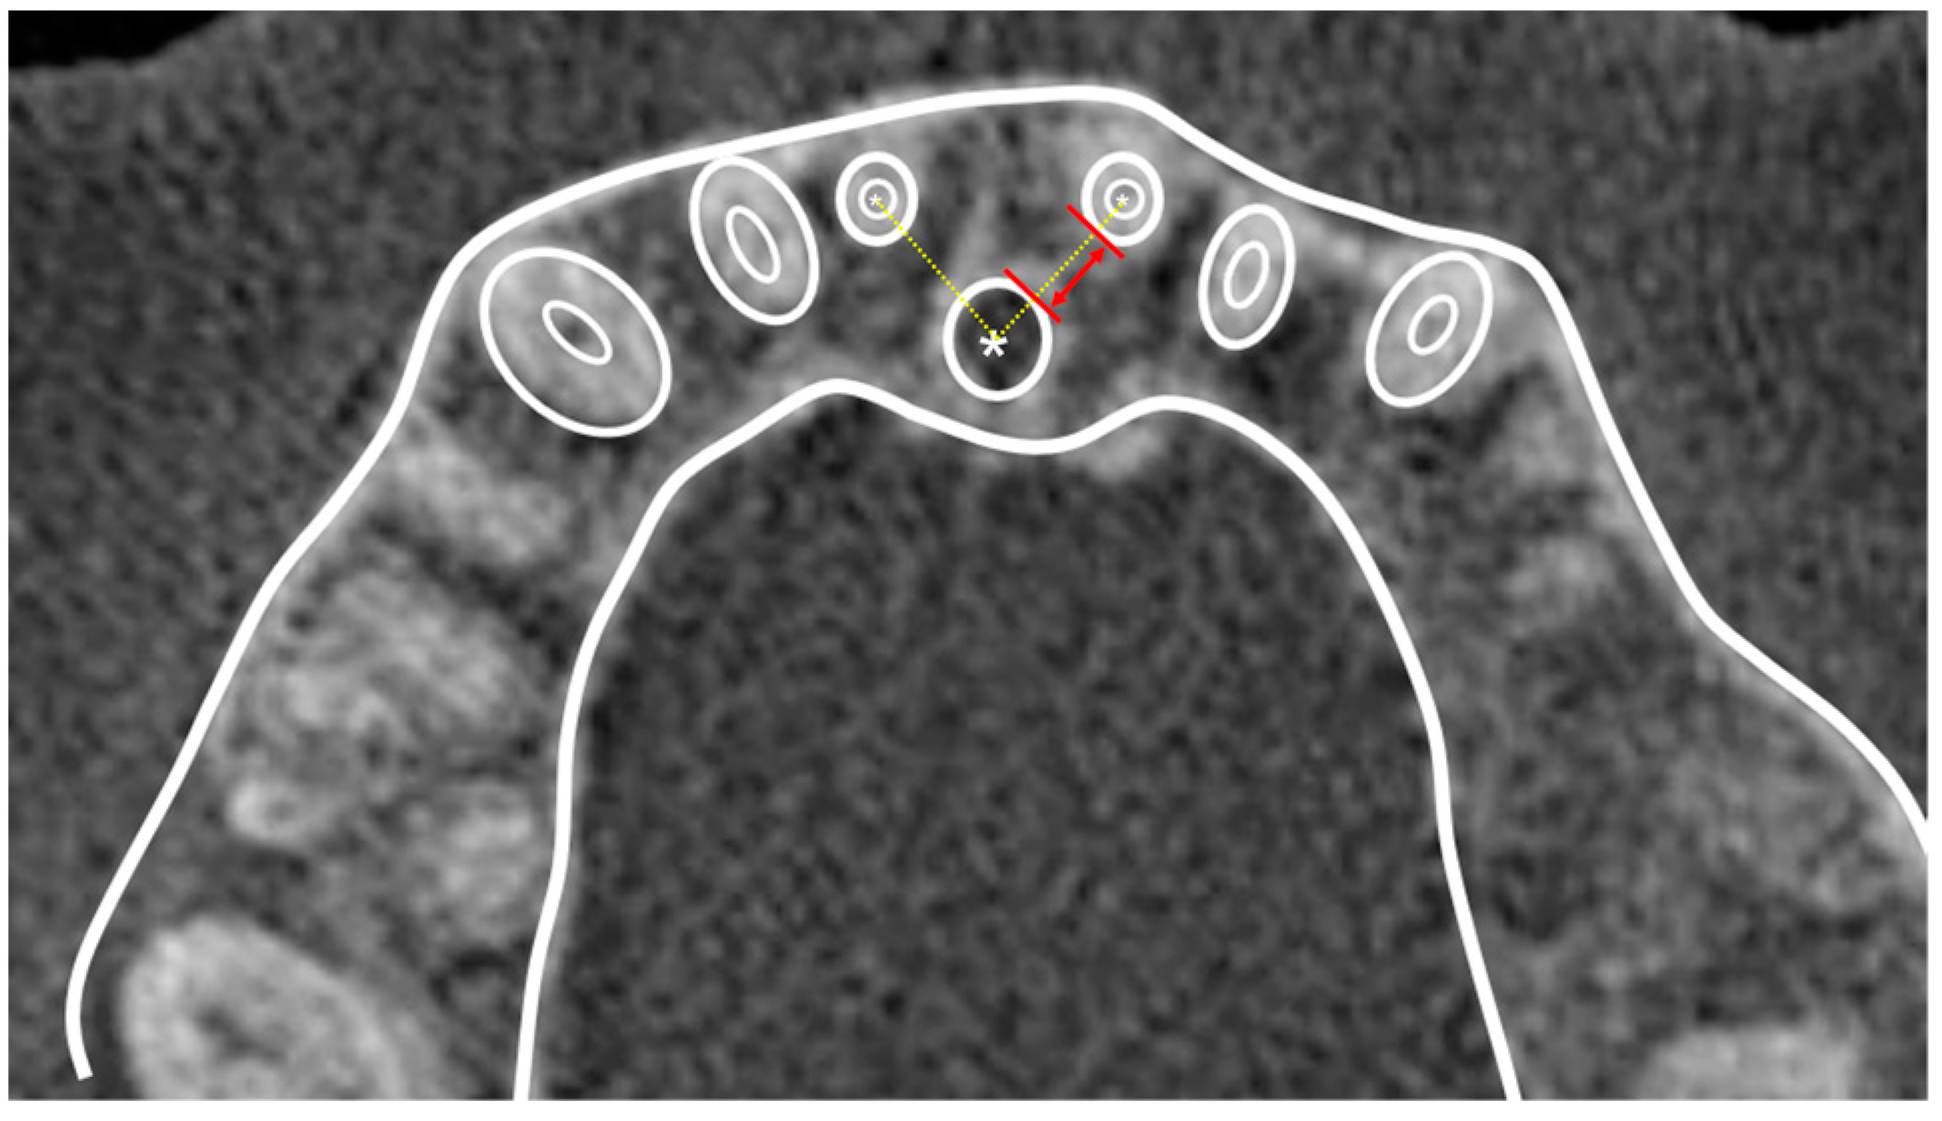

2.2. Data Acquisition and Measurements